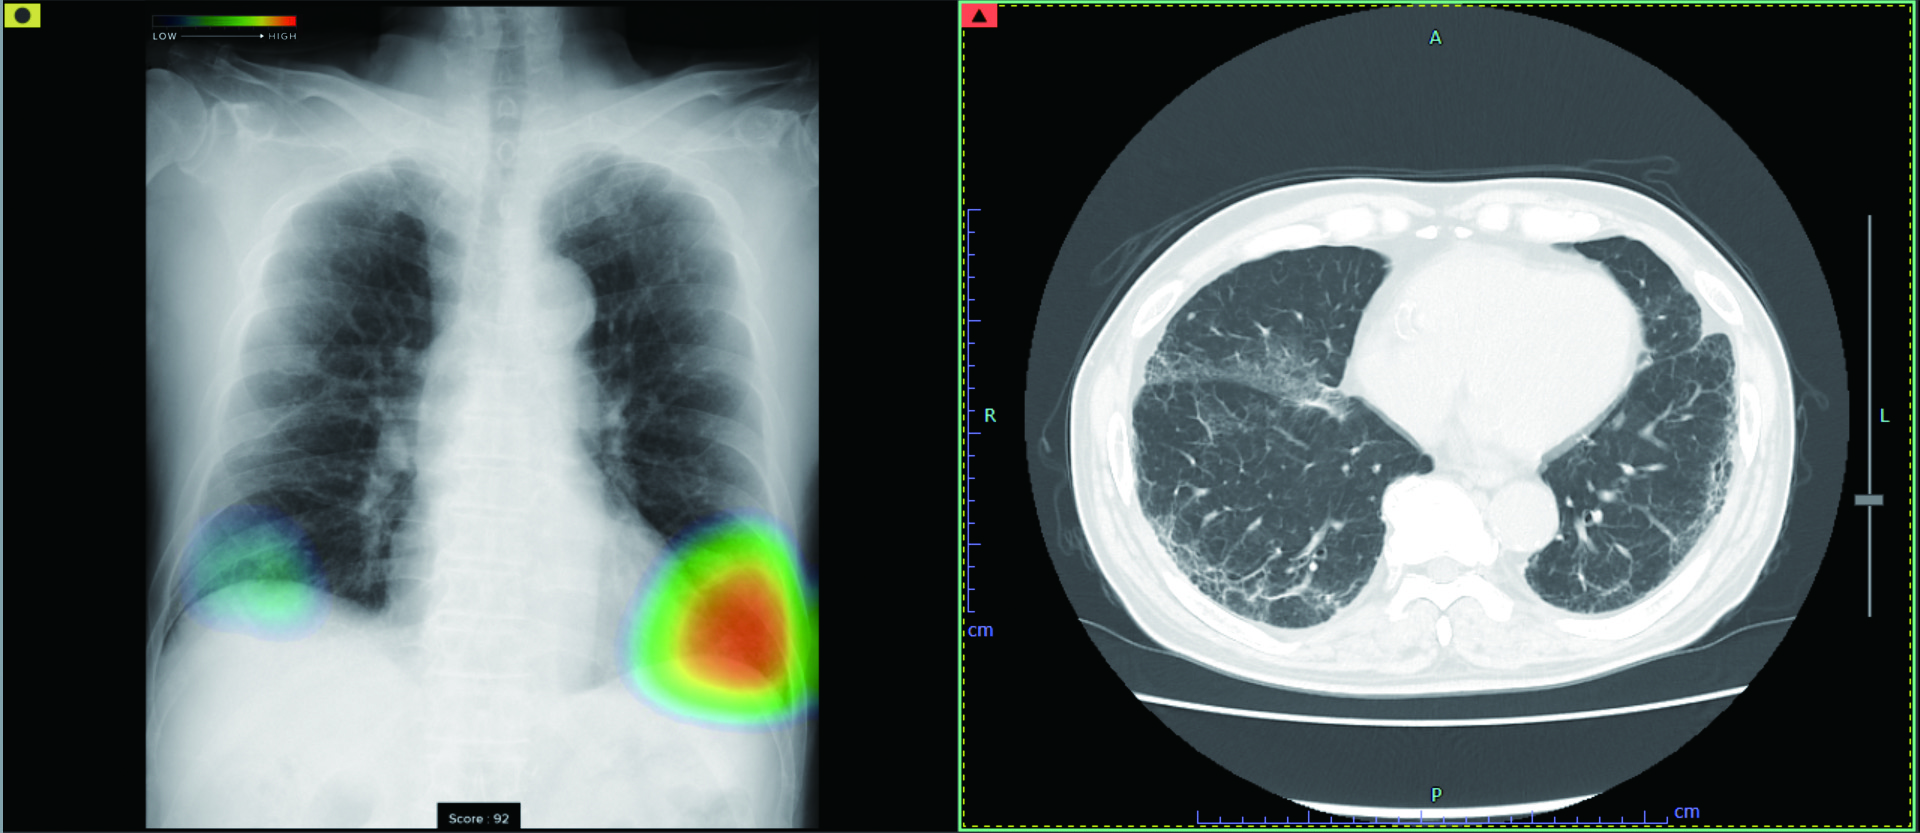

しかし、胸部レントゲン検査では、病気の発見率が低いこと、肋骨や血管を誤認してしまうなどの問題点があります。そのため人工知能(AI)技術を活用した胸部レントゲン画像病変検出ソフトCXR-AID(富士フイルム社)を使用して、胸部レントゲン画像を自動解析し、結節や腫瘤影、浸潤影、気胸などの病変が疑われる領域を検出してマーキングすることで、医師の診断をサポートします。

当クリニックでは、このAI技術を用いたソフトを導入し、健康診断や肺炎の診断などでの見落としを防ぐために活用しています。異常が認められた場合は、CTなどの精密検査を実施し、確定診断を行います。

・人工知能(AI)技術を活用した胸部レントゲン画像病変検出ソフトCXR-AID